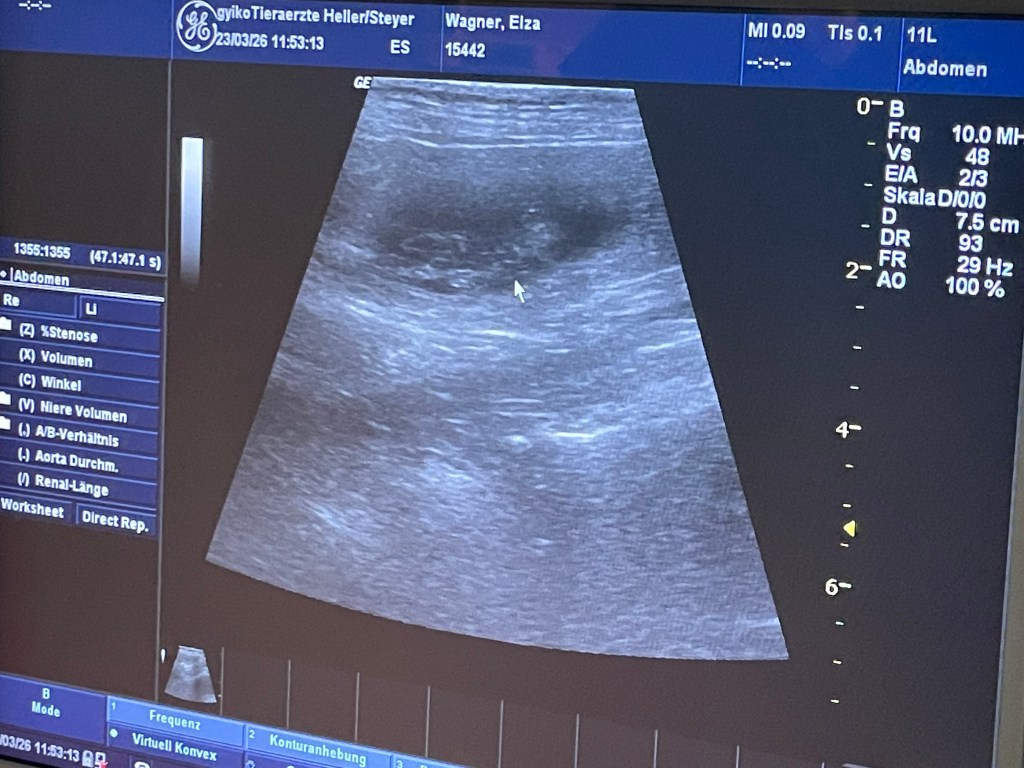

23.03.

Das Geheimnis ist gelüftet:

Elza ist tragend und es wachsen vier kleine Shelties in ihr. Wir freuen uns riesig!